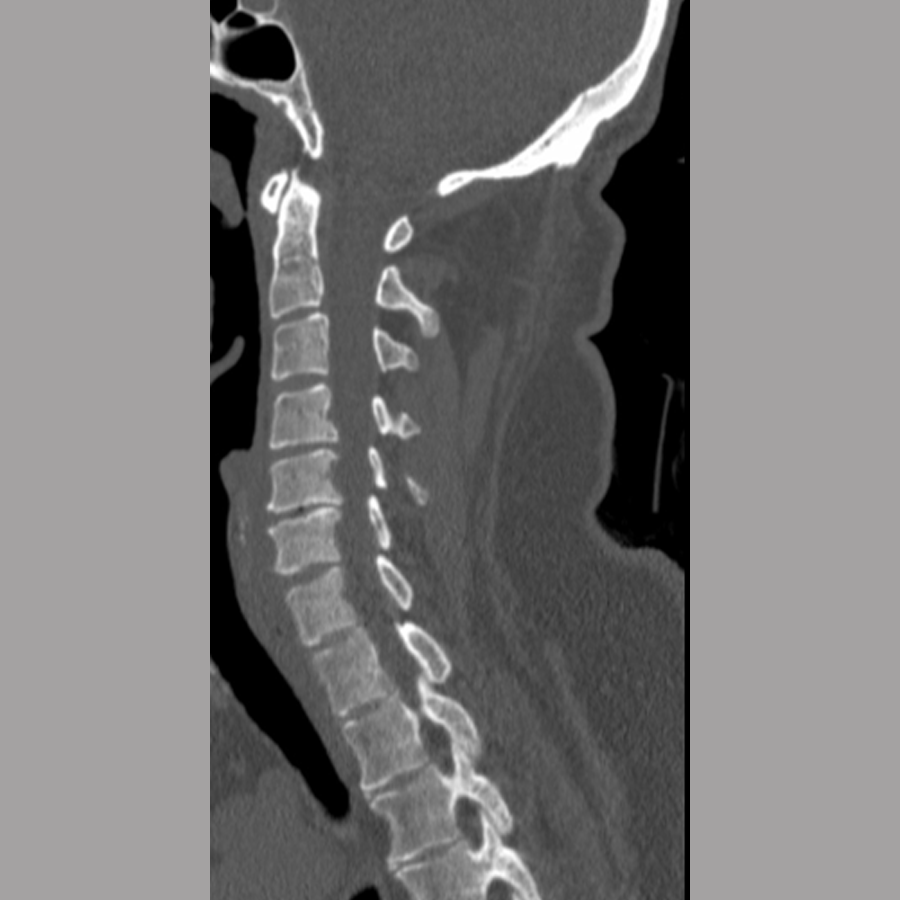

A 46-year-old man presented for evaluation of the cervical spine with magnetic resonance imaging (MRI) evidence of C4/5 mild retrolisthesis with central cord compression.

Initial injury: February 8, 2024

The patient tripped and fell down three stairs on February 8, 2024, landing face-first onto a cement floor. He was noted to have deficits to all limbs at the time of injury, with decreased grip strength. He denied neck or back pain. Magnetic resonance imaging and CT scans were performed, demonstrating C4/5 retrolisthesis, and no acute fractures but evidence of central stenosis at C4/5. The patient was offered surgery at the time of initial hospital admission but declined so that he could return to family in the US.

Imaging was conducted. Plain x-rays (Fig 7) showed:

- No acute fracture

- Evidence of degenerative disc disease at levels C5/6 with focal disc height loss.

Magnetic resonance imaging of the cervical spine performed at the time of injury (Fig 8) was reviewed and showed:

- Spinal canal narrowing at C4/5 with cord compression and associated cord edema

- Bilateral uncovertebral osteophytes with mild bilateral foraminal narrowing

- C5/6 with mild posterior disc bulging causing mild canal narrowing without cord compression

- Mild bilateral foraminal narrowing of C6/7.

A diagnosis was made of cervical spinal stenosis largely attributable to stenosis at C4/5, with lesser stenosis at C5/6 and cord compression causing sub-acute central cord syndrome. Anterior decompression was recommended to alleviate symptoms, and C4/5 anterior cervical discectomy and fusion (ACDF) was performed on March 7, 2024. Fig 9 shows postoperative imaging.